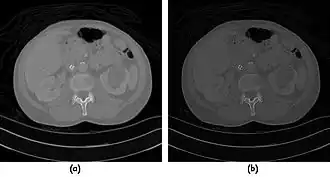

- CT Fluoroscopy (CTF) has also been referred to as Continuous CT or Real-Time CT since it involves generating tomographic images at sufficiently high frame rates to allow guidance of needle placement in small or deep-seated lesions. Applications can include biopsy of thoracic lesions, biopsy/drainage of pelvic lesions, vertebroplasty and drainage/aspiration of intracranial haematomas. The advantages of CTF include increased target accuracy and reduced procedure times[45].

- The value of N is typically 30o, 45o or 60o, with frame rates of 12, 8 and 6 frames per second, respectively. In the case of 60o updates and 6 frames per second, the delay between each image is 0.17 seconds. A Last-Image-Hold (LIH) technique can be used while the image is being updated with the resulting time lag being considered by the interventionist in terms of biopsy technique. Example images are shown in Figure 7.15.11. The display of three adjacent slices of thickness 5 mm with MDCT scanning can be used to improve visual feedback to the interventionist as the needle progresses. In addition, multi-planar reconstructions (MPR) and volume rendered 3D images can be used to enhance fine control.